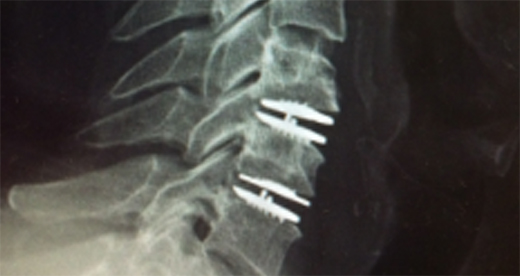

척추 유합술

복부를 최소한으로 절개하여 통증을 일으키는 손상된 뼈나 디스크를 제거하고 유합용 고정장치를 이용해 척추를 안정하게 고정시키는 수술입니다.